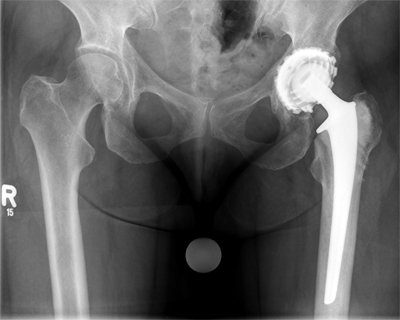

Endoprothese nach fehlgeschlagener Osteosynthese:

Bei Versagen einer Osteosynthese nach einem Knochenbruch ( Marknagel, Platte mit Schrauben, Verschraubung ) muss in seltenen Fällen ein Verfahrenwechsel durchgeführt werden. Das bedeutet, dass Schrauben oder Marknägel ect. entfernt werden und stattdessen eine Prothese implantiert wird.